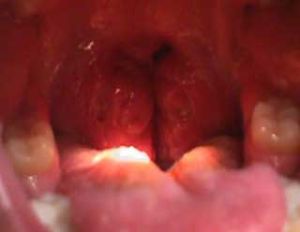

扁桃體肥大 症狀

扁桃體肥大2.鼻部症狀:扁桃體肥大常並發鼻炎、鼻竇炎。患兒有鼻塞、流涕、張口呼吸、流涎、講話時帶閉塞性鼻音、睡眠打鼾等症狀。

扁桃體肥大是由於扁桃體長期反覆被炎症刺激而形成,扁桃體肥大一旦到了一定程度會導致患者出現局部及全身的併發症,給患者的健康帶來極大威脅。因此一旦扁桃體肥大的現象,一定要及時治療。扁桃體是咽部最大的淋巴組織,在兒童時期既具有體液免疫作用,產生各種免疫球蛋白,也有一定的細胞免疫作用,一般情況下,對於小孩子的扁桃體肥大能不做手術的就不做手術。但是下面幾種是必須要手術治療的。1、頻繁發作的扁桃體炎。2、扁桃體病變全面影響兒童健康或使兒童中斷學業,以及影響聽力或呼吸時。3、扁桃體炎一年發作四次或四次以上;扁桃體炎兩年內每年發作三次或三次以上。4、扁桃體肥大引起的上呼吸道阻塞,造成嚴重打鼾,吞咽不暢,發音不清。5、有過一次或一次以上扁桃體膿腫。6、扁桃體引起了全身疾病,成為病灶性扁桃體。7、扁桃體反覆發炎引起鼻炎、中耳炎、氣管炎等反覆發作或久治不愈。扁桃體肥大手術還需要注意以下問題:1、扁桃體正在發炎時不宜切除。因為此時孩子發燒,扁桃體充血,手術後傷口容易出血或出現繼發感染。2、女孩子在月經期和月經前期不宜手術,因此時手術出血較多。3、扁桃體手術後要靠扁桃體窩內的血管自行收縮,血液凝固止血。各種原因造成凝血和血管彈性下降都可引起術後出血,因此有造血和凝血系統的疾病如血友病、再生障礙性貧血、白血病、紫癜等,都不宜手術。4、在腎炎、肝炎、風濕病、結核等疾病的活動期時不宜手術。此時手術會加重病情甚至引起嚴重的併發症。